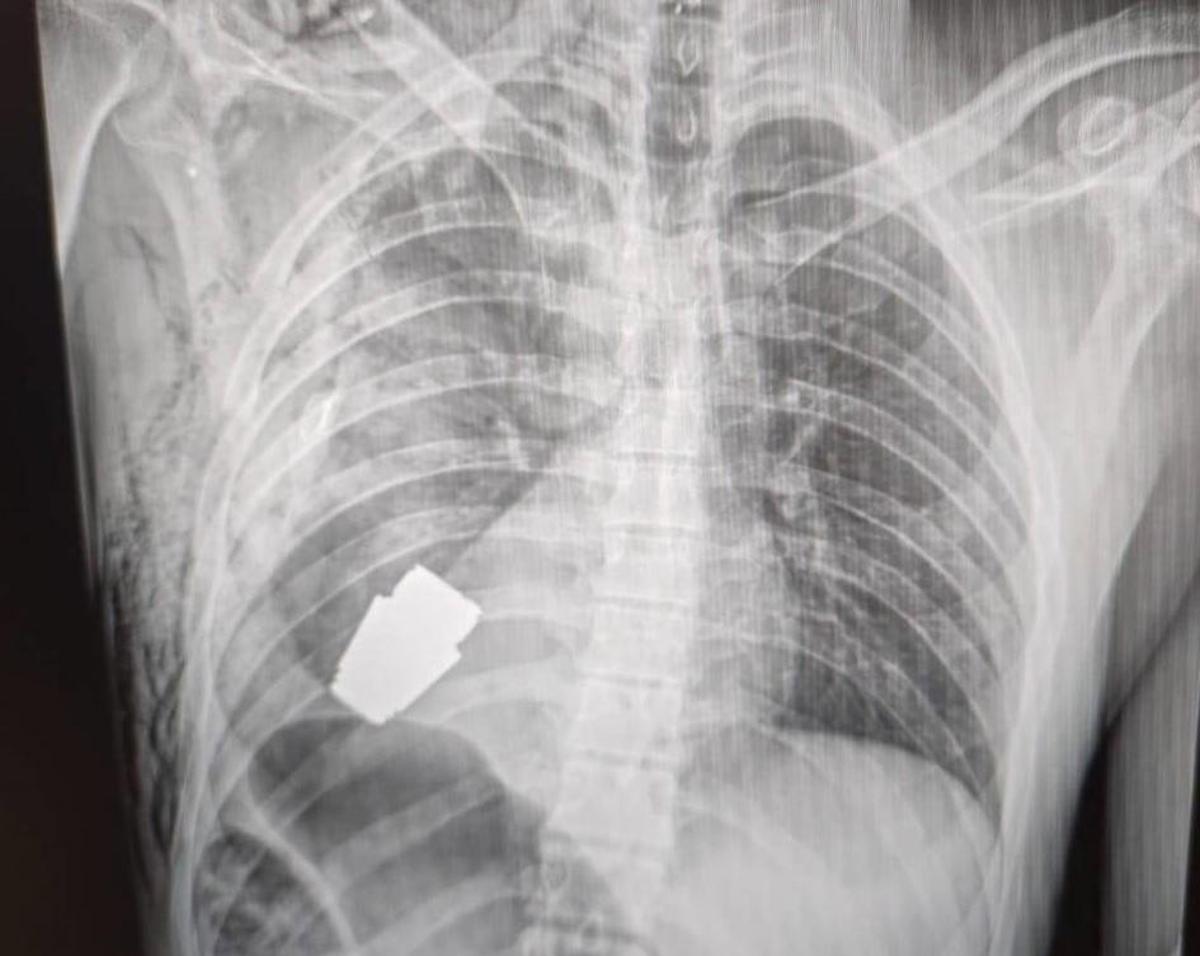

(Adnkronos) – Un’operazione per estrarre una granata non esplosa dal corpo di un soldato dell’Ucraina. Anton Gerashenko, consulente del ministero dell’Interno di Kiev, sui social pubblica la foto che documenta l’intervento eseguito dal chirurgo militare Andrii Verba. L’operazione, per estrarre la granata dal torace del militare, è stata effettuata alla presenza di due militari del genio, che in sala operatoria hanno guidato i medici per evitare che l’ordigno esplodesse.